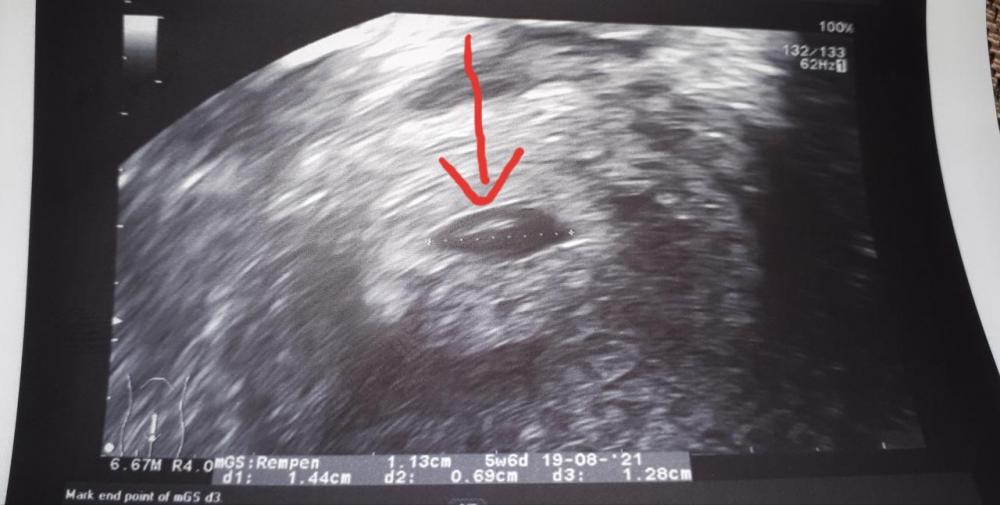

Έλα κορίτσι μου, εγώ έκανα τον πρώτο μου υπέρηχο 23 του μήνα!! Όλα πήγαν τέλεια. Η γιατρός είπε ότι όλα είναι πολύ καλά. Είδαμε την καρδούλα να χτυπάει, αλλά δεν καταφέραμε να την ακούσουμε!! Στις 12/1 που έχουμε τον δεύτερο υπέρηχο, θα την ακούσουμε, πρώτα ο Θεός!!! Σας βάζω φωτο, να καμαρωσετε το παιδί μου!! 🤣🤣🤣🤣

@Μαριλου1 @Avgoulla Καλημέρα!!! Εγώ χθες έκανα πρώτο υπέρηχο, 6 εβδομάδων είμαι. Είδαμε καρδούλα!!! ΠΗΤ έχω 16 με 19 Αυγουστου!! -

Είδαμε το σπορακι μας!!!! Χτυπάει η καρδούλα, την είδαμε να χτυπάει!! Απλά δεν την ακούσαμε!! Όλα καλά, όλα τέλεια είπε η γιατρός!!! Επόμενο ραντεβού 12/1 !!!! -